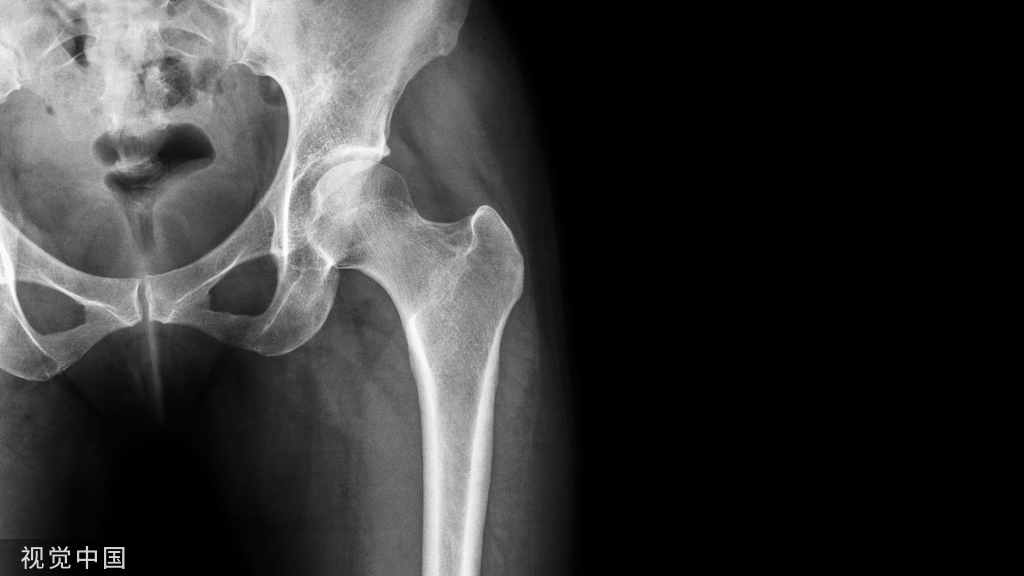

侧位:a1、a2代表双侧坐骨大孔;b1、b2:代表骶骨翼

(1)骶岬在S1椎弓根块的前方,而骶骨翼是骶骨岬与骶髂关节前面之间的凹陷,走向骶岬的螺钉容易损伤前方结构;髂骨增厚处和S1椎体是骶髂螺钉固定点。

(2)S1骶孔的一半以上由S1椎体形成,S1神经根管从S1 骶孔的下、前和外侧穿过,如果螺钉位于S1椎体的下半部,则必须指向S1神经根管的前方,偏后则会损伤S1神经根。

(3)S1节段周围的结构有:S1神经根管和S1骶孔在S1椎弓根块的下缘,S1椎体后方是马尾神经,骶骨翼前方是髂内血管、L5神经根 、输尿管;膀胱在S1椎体的前方,S1椎体的上方是椎间盘,以上重要结构都不能损伤。